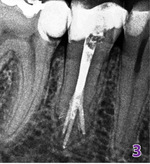

Dzięki szerokiemu opracowaniu kanałów możliwe było ich właściwe wypełnienie. Aby zrobić to poprawnie, musimy pamiętać, by nie doszło do przypadkowego dostania się gutaperki do kanału, który nie został jeszcze wypełniony. Dlatego wypełnienie ćwiekiem gutaperkowym musi zostać poprzedzone sprawdzeniem długości roboczej. Również odcięcie ćwieka na odpowiedniej głębokości ma istotne znaczenie. Zawsze powinno mieć miejsce w kanale, który jest aktualnie wypełniany, a wejście pluggera musi być powtarzalne. W tym celu użyto bezprzewodowego systemu firmy B&L. Ostateczne wypełnienie kanału głównego wykonano ciepłą gutaperką podaną z pistoletu (fot. 3).